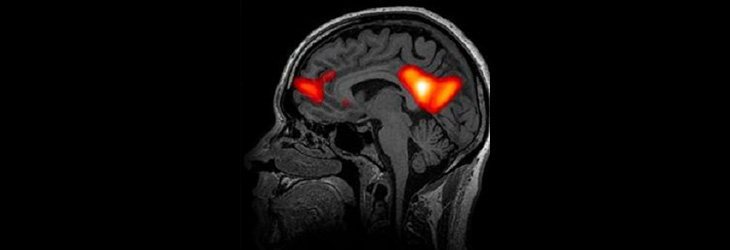

Advances in Minimally Invasive Neurosurgery Keyhole and endoscopic approaches for cranial and spinal surgeries. Role of robotic-assisted neurosurgery in precision interventions. Functional Neurosurgery Innovations in deep brain stimulation (DBS) for movement disorders and psychiatric conditions. Neurosurgical approaches to epilepsy: Outcomes and emerging techniques. Neuro-Oncological Surgery Surgical strategies for gliomas, meningiomas, and metastatic brain tumors. Integration […]